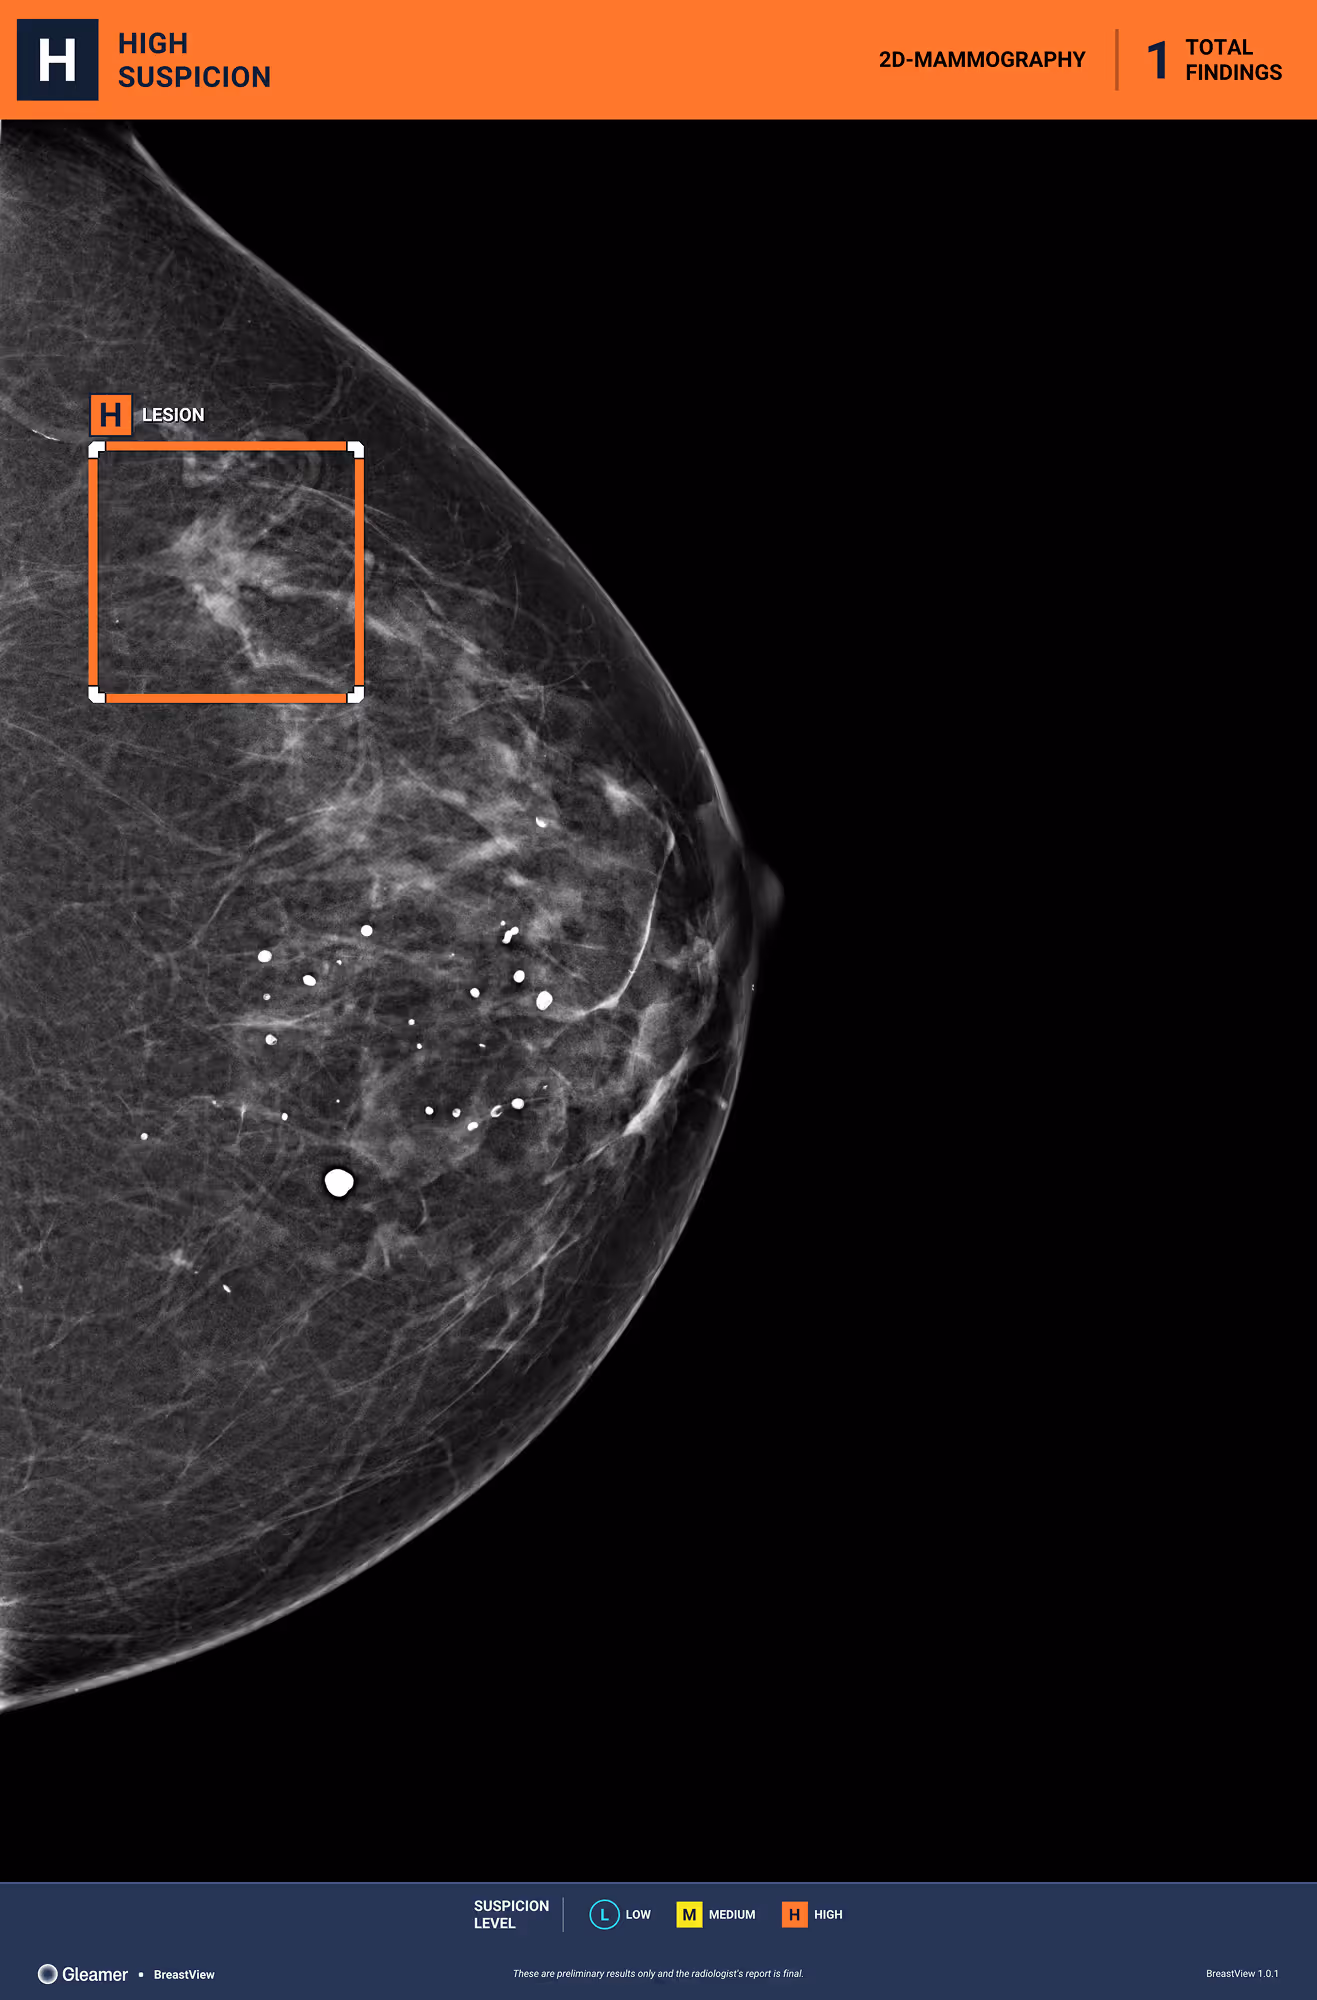

63 y.o. patient presenting as part of organized screening.

Results

BreastView detected a lesion that was a non-specific infiltrating carcinoma